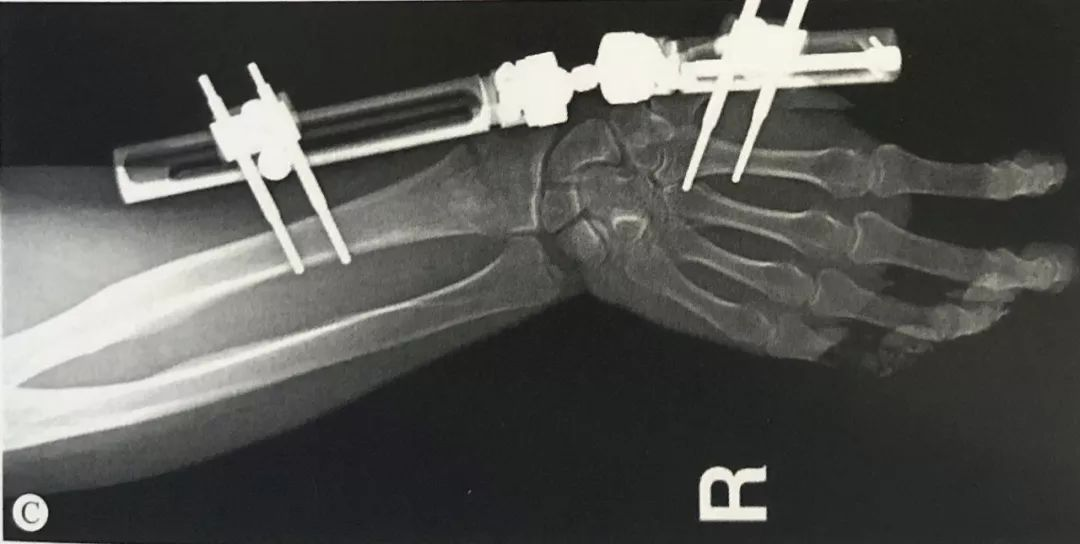

与掌骨螺钉在同一平面,套筒保护软组织导向器引导下置入2枚3mm Schanz螺钉。

骨折的复位与固定:

手法牵引复位C形臂透视下检查骨折的复位情况。

跨腕关节的外固定,难以完全恢复掌倾角,可以结合Kapandji针辅助复位、固定。

对于桡骨茎突骨折的患者,可以结合桡骨茎突克氏针固定。

维持复位的情况下,连接外固定支架,将外固定架旋转中心同腕关节旋转中心置于同一轴线上。

正侧位透视,检查桡骨长度、掌倾角和尺偏角是否恢复,调整固定角度直至骨折复位满意。